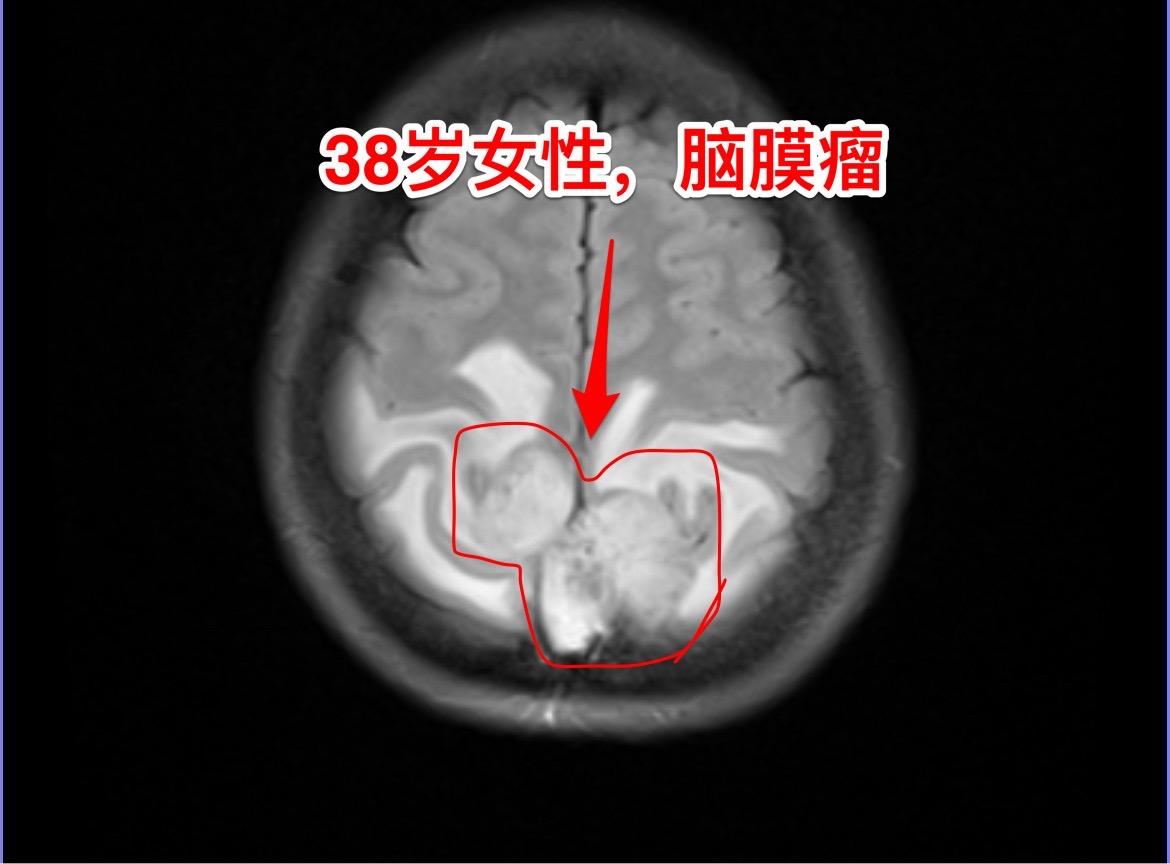

脑膜瘤的病理诊断—-需要格外关注。绝大多数的脑膜瘤都是良性肿瘤,小部分脑膜瘤是非典型的,也有一部分脑膜瘤呈恶性。 这个38岁湖北女性,因为头痛发现脑膜瘤。磁共振显示脑膜瘤周围有大范围的脑水肿,手术过程中发现肿瘤侵蚀了颅骨,将颅骨吃透了。直观的感受是:这个脑膜瘤是不是呈恶性趋势? 病理报告这个脑膜瘤是WHO1级,是良性肿瘤。只是Ki67指标稍高,以后需要定期复查。 这个病人手术后没有出现下肢活动无力症状,很快就能下地活动。这个位置的手术比颅咽管瘤手术要轻松许多,